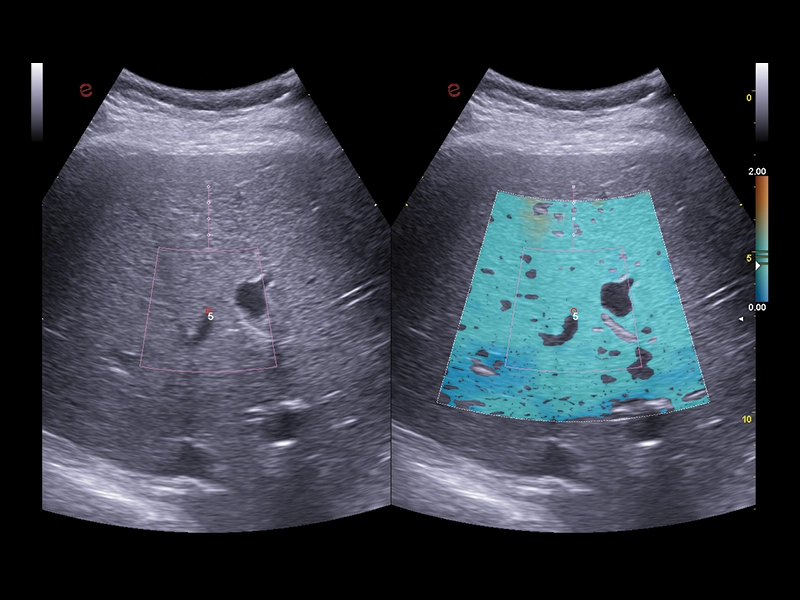

MyLab™C30 - QElaxto 2D liver

MyLab™C30 - QElaxto 2D liver

MyLab™9 Platform - QElaXto 2D shearwave elastography in liver

MyLab™9 Platform - QElaXto 2D shearwave elastography in liver